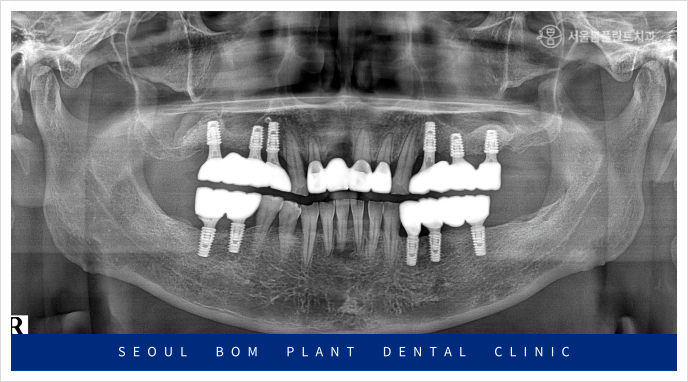

정밀한 검사를 위해

파노라마 사진을 촬영해 보았더니

잇몸뼈 소실로 많이 약해져 있는 상태라

다시 임플란트를 식립하기에는

무리가 있었습니다.

위턱 오른쪽 앞니(#11)의 경우

환자분과 충분한 상담을 통해

양옆의 치아를 이용한

브릿지 보철물을

진행하기로 계획하였는데요.

앞니 외에도 치료가 필요한 부위가

많이 있었는데요.

빨간색 동그라미 표시의

위턱 왼쪽 첫 번째 큰 어금니(#26)와

아래턱 왼쪽 작은 어금니(#34,35)

아래턱 오른쪽 첫 번째 큰 어금니(#46)가

뿌리 끝 염증과 함께 동요도도 심한 상태라

발치가 불가피한 상황이었습니다.

먼저 왼쪽 위턱의

기존 상실된 부위부터

임플란트 식립을 진행하였으며

잇몸이 아무는 정도에 따라

아래턱 오른쪽과 왼쪽에 차례대로

임플란트 식립을 진행하였는데요.

발치를 했던 부위이다 보니

잔존 치조골의 양이 부족하여

잇몸뼈를 충분히 보완한 뒤

안정적으로 임플란트 식립을

도와드렸습니다.

위턱의 오른쪽 임플란트도 진행하였는데요.

위턱 오른쪽 어금니 부위의 경우

잔존 치조골과 상악동과의 거리가

가깝게 위치해 있어

임플란트를 식립하기에는

수직적인 거리가 부족하여

이 경우 상악동 거상술을 동반한

뼈이식이 필요하였는데요.